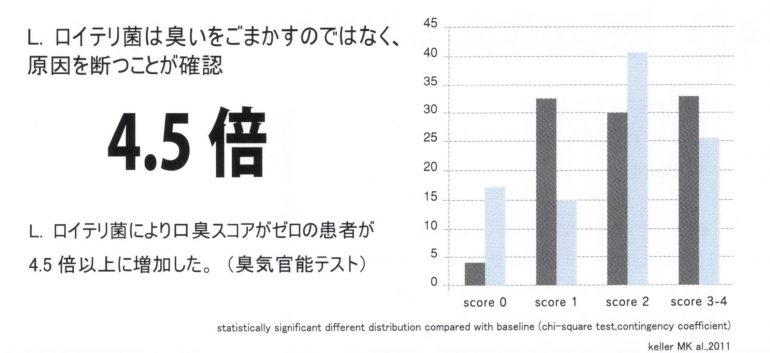

口臭を減少させる

1週間ほど摂取することで、歯周病菌か起床時のお口のネバネバ(不快感)などを軽減し、口臭が気にならなくなります。